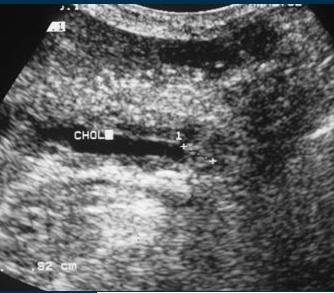

Echographie percutane

: Images echographiques du cholangite

infectueuse

aigue : Dilatation des voie biliaire intra et

extrahepatique , depasse 8mm avec voie

extrahepatique et 4mm des voies intrahepatique ,

Epaissisement de hypoattenuant de sa paroi . Image

de calcul canalicules et parfois de la

presence de pus intracanalaire .